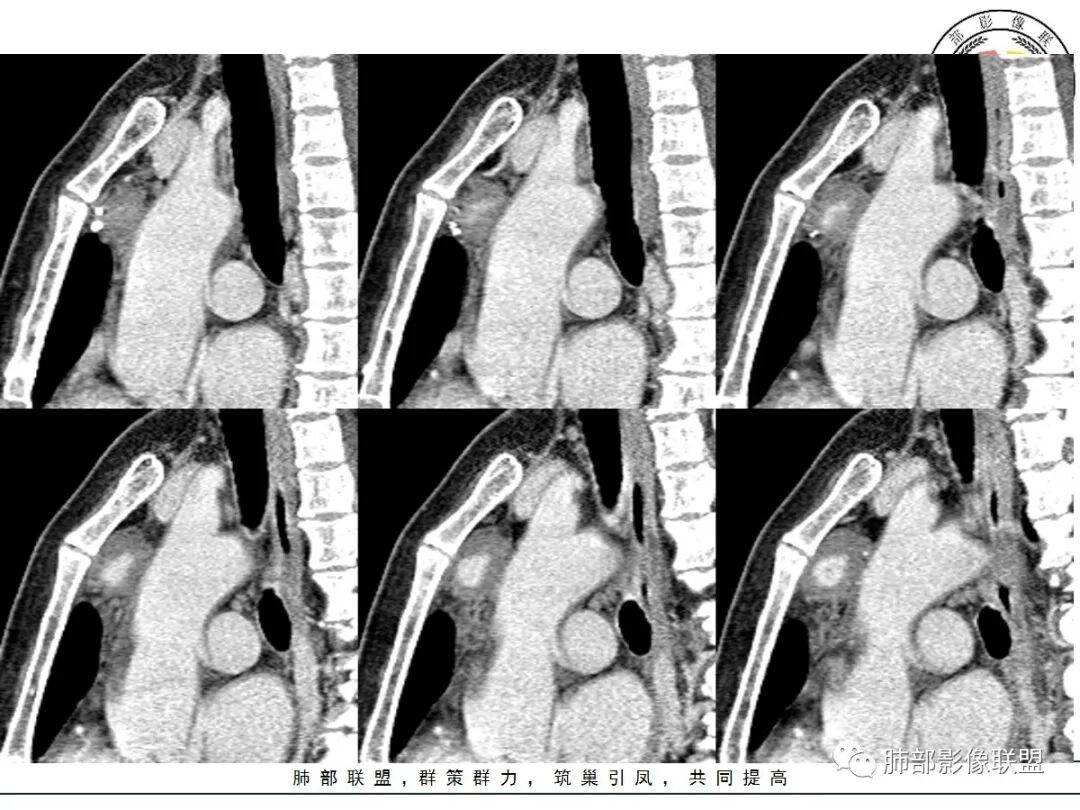

红星:女性病人48岁,前上纵隔,类圆形的实性病变,平扫密度比较均匀,周围卷见点状的钙化灶,增强扫描明显的强化, 多时相扫描中心可见跟大血管强化幅度一致的结节灶。常规胸腺瘤?鉴别血管瘤?

周太狼:中年女性,前纵隔肿块,边界清,内不规则钙化灶,增强中央明显强化,与邻近血管强化程度相似。纵隔内无明显增大淋巴结。考虑良性或低度恶性病变。疾病谱:CD、副节、血管瘤、胸腺瘤/癌。个人倾向于CD或血管瘤可能大一些。

三个石头:前纵隔占位,残余胸腺组织可见,边缘钙化,增强中央出现与血管同步强化结节,病灶延迟强化。脉管瘤?胸腺瘤?血管瘤?异位甲状腺?

南边:定位前纵隔没问题

边缘多发条状、线样、结节状钙化

南边:边界尚清,位于残留胸腺组织内

中央结节状强化, 类似于血管强化

定性:偏良性病变,血管瘤?胸腺瘤?

前纵隔海绵状血管瘤的影像学特征包括:①发生于前纵隔的圆形、类圆形、不规则肿块影,边界清晰,与邻近结构分界清晰;②CT上呈稍低密度影,内见小结节状、小片状、针尖状的钙化灶,钙化灶、静脉石影是海绵状血管瘤的特征性表现。③增强后大多数肿块可显示肿块的范围及供血情况,动脉期病灶边缘呈点片状强化,静脉期及延迟期逐步向内填充,呈渐进性强化等典型特征,部分不强化或轻度强化,部分增强 后片状强化,强化程度与邻近血管相仿;血管瘤强化方式与肿块内组织成分、血窦内血栓、血流等因素有关;Moran等研究表明,肿块强化不均匀或呈轻度强化的原因可能与扩张的血窦腔内组织平滑肌增殖及炎性纤维化有关;肿块血管样强化可提示海绵状血管瘤。前纵隔海绵状血管瘤需与畸胎瘤、胸腺瘤、胸内甲腺肿、神经内分泌肿瘤等进行鉴 别 断:①畸胎瘤多呈混杂密度影,内有脂肪、毛发、钙化灶及水样密度;②胸腺瘤呈结节状、团块状影,密度较均匀,增强后强化较均匀,与周围组织分界清晰;③胸内甲状腺肿位于前上纵隔,平扫密度常较高,可见其上端与颈部甲状腺相连;④神经内分泌肿瘤多伴坏死囊变,点片状钙化,形态常呈分叶状或 不规则形,增强后肿瘤实性部分强化显著。

综上所述,海绵状血管瘤发生在纵隔非常罕见,且缺乏典型的临床症状及特异性影像, 应从肿块的位 置、大小、形态、与周围组织的 关 系 以及CT平扫、增强特点进行分析,如前纵隔肿块内有钙化灶、静脉石、增强后点片状血管样强化及渐进性强化等特点,应考虑纵隔海绵状血管瘤的可能;薄层CT及其多平面重组有利于发现细小钙化灶,而动态增强CT扫描能更好显示肿块内血管强化,有助于术前诊断与鉴别诊断。